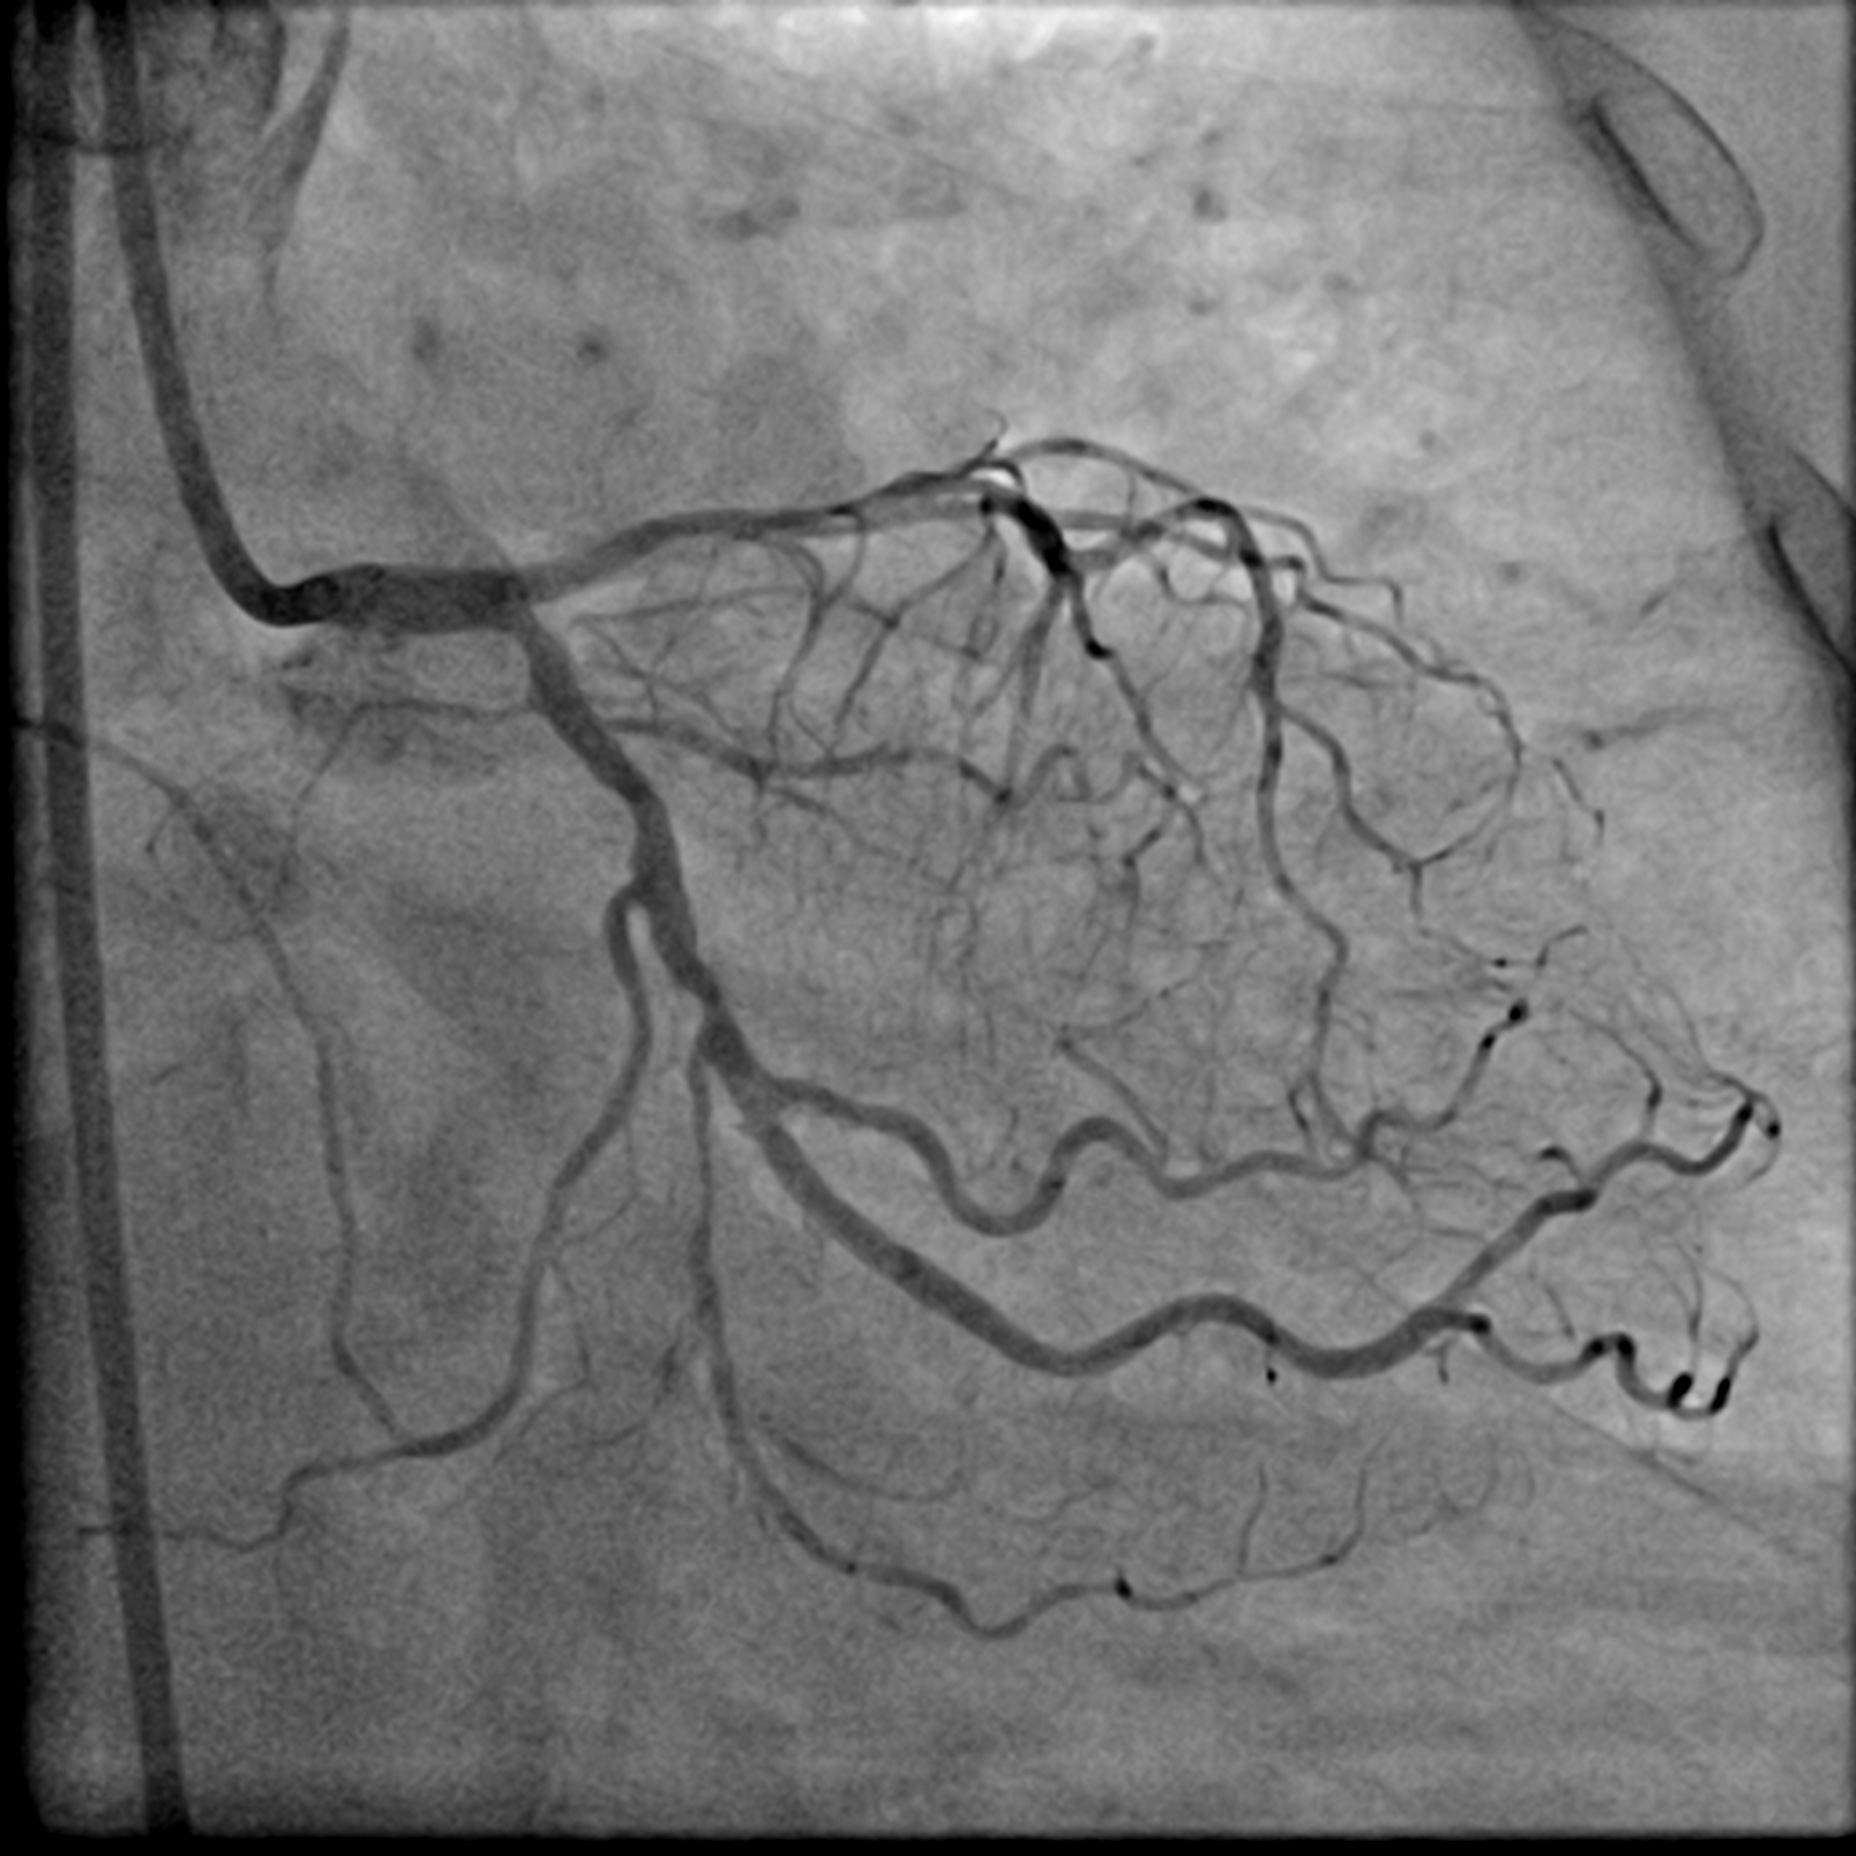

After positioning the ViperWire in the distal LAD, the OAS was delivered, and calcium debulking at low speed was performed safely. Afterward, the LAD was pre-dilated with a 2.5 mm scoring balloon and a 3.5 mm cutting balloon, while the LCx was pre-dilated with a 3.0 mm cutting balloon. A repeat angiogram revealed an Ellis 3 perforation in the proximal LAD, accompanied by a drop in the patient's blood pressure. Expeditiously, a 3.0 mm balloon was inflated at the perforation site, and its location was confirmed with an angiogram, which indicated immediate reduction of the perforation. A pigtail catheter was inserted simultaneously under echocardiographic guidance, and autologous blood transfusion was initiated. The perforation was covered with a 2.5 mm x 20 mm covered stent and post-dilated with a 3.0 mm NC balloon. This reduced the leak, but significant flow persisted. IVUS showed a gap between the stent strut and vessel wall near the LAD carina, allowing for persistent leakage. The covered stent was further post-dilated with a 3.5 mm NC balloon and a hugging balloon technique using two 2.5 mm balloons. These measures failed, as the maximal expansion of the 2.5 mm covered stent is limited to 3.0 mm. A Kissing Balloon Technique (KBT) was attempted at the bifurcation, but it proved futile. Finally, a second 3.5 mm covered stent was placed proximally, which successfully sealed the perforation, leaving only a trivial leak. The hemoperricardium resolved after 24 hours.